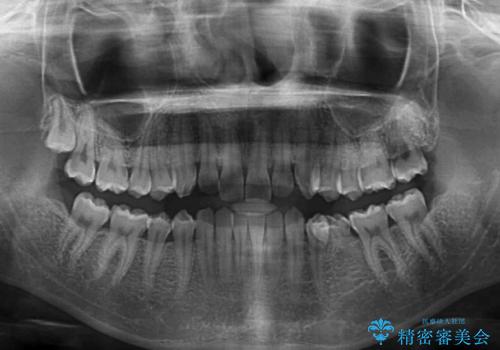

- 前歯の叢生と、奥歯の咬み合わせの悪さを気にして来院された患者様です。

左下には後続永久歯の欠損した乳歯が残存しており、叢生を相まって咬合関係が乱れていました。

乳歯は抜歯し、インビザラインにて矯正治療を行いながら、並行してインプラントによる補綴治療を行うこととしました。

矯正治療が終わるタイミングに合わせてインプラントの埋入を行っていたので、矯正治療を終了すると同時にセラミック補綴治療を行えました。